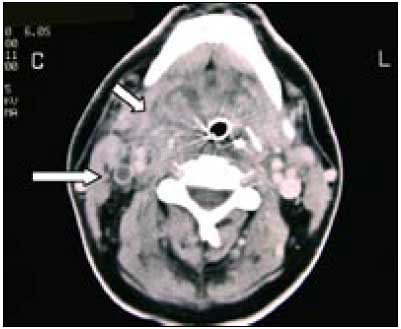

Voru þessar bakteríur sendar á sýklafræðideild Landspítala til frekari greiningar. Þar var staðfest að um var að ræða loftfælna Gram neikvæða stafi sem ekki gerjuðu sykra (asaccharolytic), líklega Fusobacterium sp. Gott næmi var fyrir penicillíni, klindamycíni og metronídazóli. Ákveðið var að senda þær til Statens Seruminstitut í Kaupmannahöfn, til staðfestingar og frekari greiningar. Á fimmta degi eftir innlögn er sogað var úr hálsi sjúklings áður en skipt skyldi um barkarennu, vall fram talsvert magn af illalyktandi greftri í munnhol hans. Tölvusneiðmynd af hálsi (mynd 2) sýndi þá mikla bólgu í kokeitlabeðnum hægra megin og hliðrun á barkarennu til vinstri yfir miðlínu. Ekki sást nein ígerð né fyrirferðaraukning í aftankoksrými (retropharyngealt). Ekkert loft sást umhverfis barkarennuna og benti það til þess að loftvegurinn væri verulega þrengdur. Einnig kom í ljós að hægri innri hóstarbláæð (vena jugularis interna dxt.) var algerlega stífluð af segamyndun á öllu hálssvæðinu, alveg upp að kúpubotni.

Tölvusneiðmynd af höfði sýndi enga skuggaefnisfyllingu í hægri bugastokk (sinus sigmoideus), var það talið merki um segafyllingu. Seginn teygði sig upp að mótum bugastokks og þverstokks (sinus transversus). Tölvusneiðmynd af brjóstkassa (CT thorax) sýndi fjölmarga misstóra hnúta, 1-3 cm í þvermál. Sumir hnútanna voru loftfylltir og var þetta túlkað sem sýktir blóðsegar til lungna (mynd 3). Haldið var áfram meðferð með ceftríaxón og klindamýsín og fór ástand hans smám saman batnandi. CRP lækkaði eftir að graftarkýli í hálsi hafði tæmst. Barkarenna var fjarlægð á 8. degi og hann útskrifaðist af gjörgæslu yfir á lyfjadeild á 13. degi eftir innlögn. Sýklalyfjameðferð var hætt á 18. degi. Hafði hann þá fengið ceftríaxón í 18 daga og klindamýsín í 12 daga.